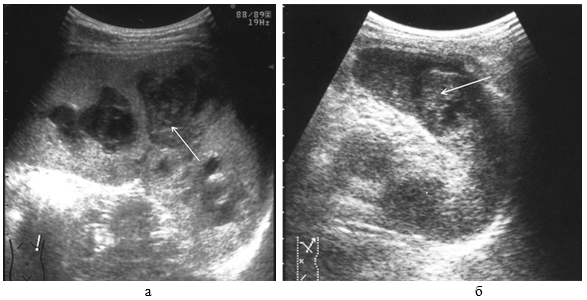

Ушибы селезенки сопровождаются интерстициальным отеком и геморрагическим пропитыванием тканей. Прямыми эхографическими признаками в первые 3–5 часов после травмы являются снижение эхогенности паренхимы и четкости контура органа, а также «разреженность» эхоструктуры паренхимы. Геморрагическое пропитывание паренхимы манифестировало наличием гиперэхогенных зон с нечеткими размытыми контурами в области повреждения (рис. 1). Характерно увеличение размеров всей селезенки или преимущественно поврежденного сегмента с нарушением ее конфигурации. Результаты цветового допплеровского картирования свидетельствуют о снижении кровотока, степень которого коррелирует с выраженностью эхографических проявлений отека паренхимы.

Рис. 1. Ушиб селезенки. Зона геморрагического пропитывания указана стрелками.